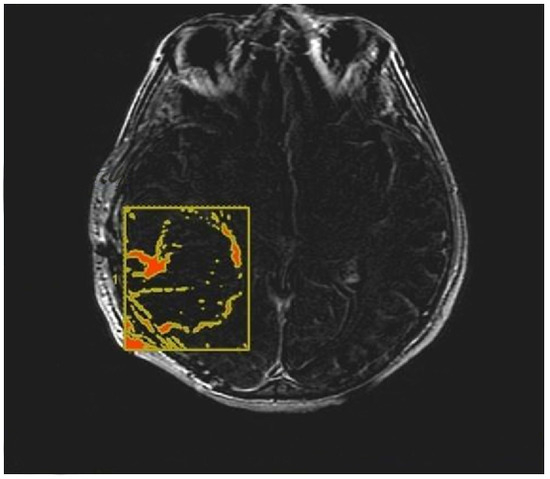

- Morphological appearance: We divided GB lesions into three categories based on the enhancing wall thickness: thin, <3 mm; thin-nodular, when the enhancing wall showed focal thickenings > 3 mm; and nodular, when solid appearance was predominant and intratumoral necrosis was absent or <1.5 cm3. A total of 11 (13%) masses showed a thin pattern, 51 (58%) showed a thin-nodular pattern, and 25 (29%) showed a nodular pattern.